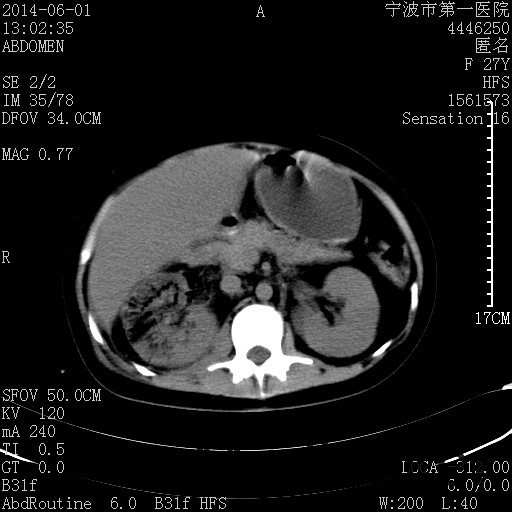

患者,女,27岁,因“右下腹疼痛伴呕吐2天”入院 患者无明显诱因出现右下腹疼痛伴呕吐、发热,体温最高39度,急诊CT示:右肾集气,考虑气性肾盂肾炎。

查体: 右肾区叩击痛,右下腹压痛,无反跳痛。 辅助检查: 空腹血糖9.7mmo/L,餐后血糖18mmol/L 血常规:白细胞 11.3*109/L, 中性百分比 77.4%, 血红蛋白 8g/L, 血小板 319*109/L 尿常规 WBC+++ 生化:白蛋白 37.5g/L,肝肾功能正常 泌尿系CT:右肾集气

诊断为“气性肾盂肾炎,感染性休克,糖尿病酮症酸中毒” 血、尿、脓液培养均示“克雷伯杆菌” 入院第2天行“右双J管置入术” 入院第3天、7天行“右肾穿刺造瘘术” 入院1月行“右肾切除术” 术后顺利康复出院。